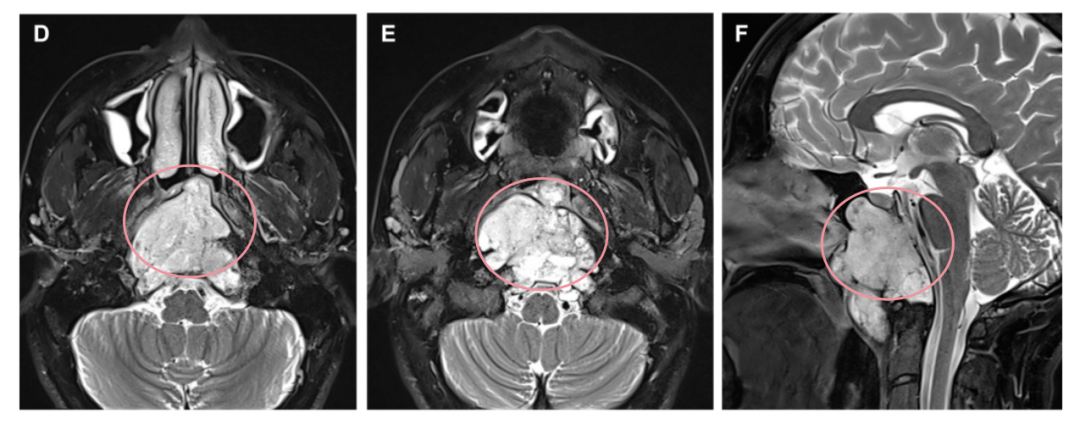

一位48歲的女士確診為斜坡脊索瘤,外展神經(jīng)麻痹,看東西時(shí)常常出現(xiàn)斜視和復(fù)視,因?yàn)閺?fù)視走路也不穩(wěn)……腫瘤侵襲廣泛,已經(jīng)延伸到了巖尖、海綿竇、頸靜脈孔等部位,直至硬膜內(nèi)。位置深,侵襲范圍廣,安全全切不易。

最終手術(shù)順利完成,術(shù)后 MRI 證實(shí)腫瘤被完全切除(箭頭所指為填充的脂肪),同時(shí)鼻窩保持完整。在2個(gè)月的隨訪中,內(nèi)鏡檢查沒(méi)有發(fā)現(xiàn)結(jié)痂,患者也沒(méi)有抱怨任何鼻腔不適。

通過(guò)單鼻孔入路,福教授為Roger成功完成了手術(shù),術(shù)后MRI顯示腫瘤被完全切除。術(shù)中同樣采用了鼻粘膜修復(fù)技術(shù),保證了術(shù)后的生活質(zhì)量。

術(shù)后MRI影像明確腫瘤全切情況,以及用于重建的自體脂肪